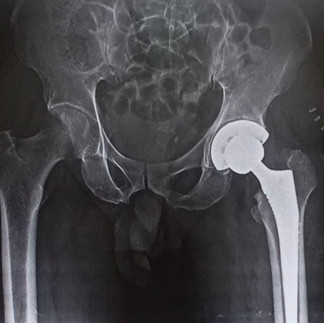

On evaluation, he was diagnosed with advanced osteoarthritis of the hip—a condition caused by wear and tear of the joint due to age and years of physical activity. In such advanced stages, conservative treatments no longer provide relief, and Total Hip Replacement (THR) remains the best option to restore mobility and eliminate pain.

Mr. Kumar courageously opted for surgery. Post-operatively, his recovery was remarkable—he was able to walk the very next day, pain-free and with a smile. For someone who had been living with constant pain, this was nothing short of life-changing.